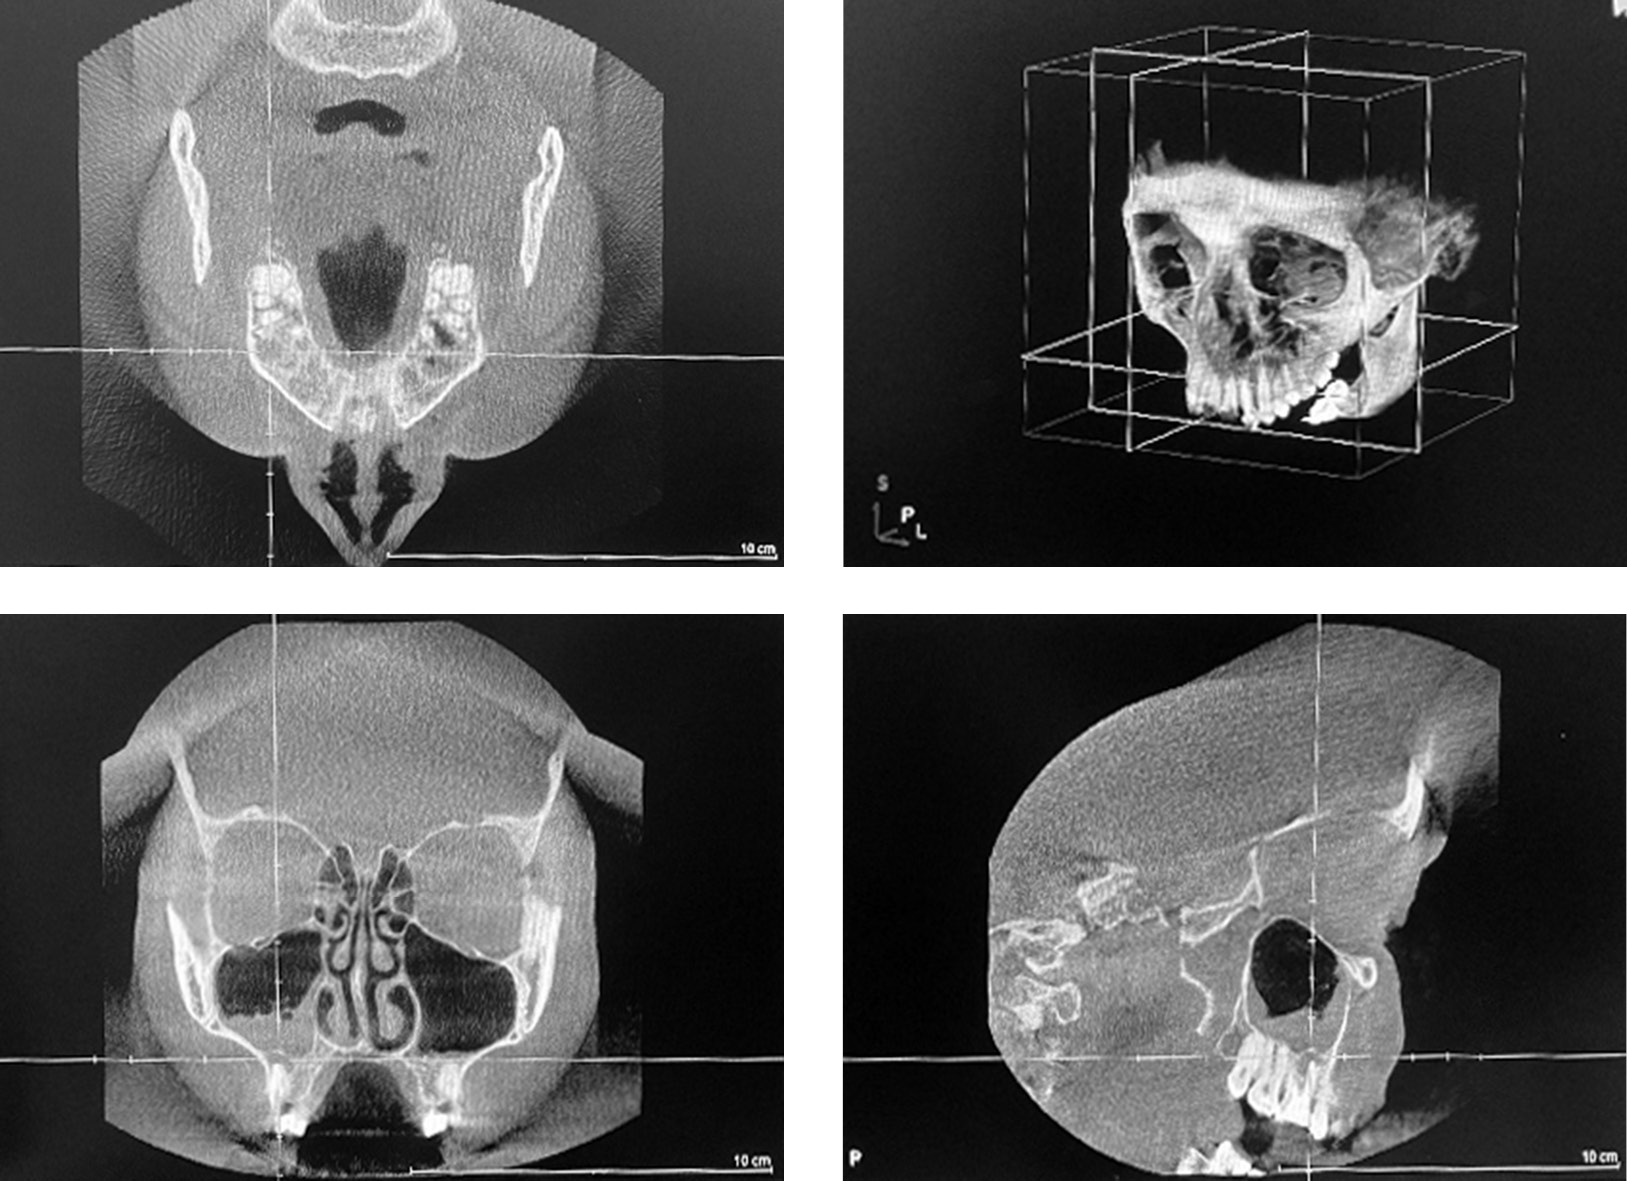

Patient A, 58 years old, was urgently admitted to the Clinic of Otolaryngology of the First Pavlov State Medical University of St. Petersburg with complaints of nasal congestion, difficulty nasal breathing, headache, sensation of pressure and fullness in the maxillary sinuses, and food and water leaking from mouth into the nose. Medical history revealed that the patient had teeth 1.4, 1.5, 1.6 removed approximately a year ago, after which acute right sinusitis developed and an oroantral communication formed. The patient had nasal breathing problems for the past 25 years. The patient had 3 episodes of right maxillary sinusitis within one year. The patient had an episode of severe stress and hypothermia one week prior to hospitalization. Cone beam computed tomography showed subtotal shadowing of both maxillary sinuses with an exudative component, total shadowing of the ethmoidal labyrinth cells, a defect in the right alveolar process of the upper jaw up to 10 mm in the projection of the missing teeth 1.5, 1.6 due to oroantral communication (Figure 3). Objective nasal examination revealed edematous and hyperemic mucosa, moderate bilateral mucopurulent discharge, deflected nasal septum, and a positive right nasal-oral test. After systemic antibacterial therapy and puncture, the acute inflammation was treated, but right oroantral communication and nasal breathing difficulties persisted. The patient underwent combined multidisciplinary treatment of the intranasal structures, including endoscopic septoplasty, endoscopic right maxillary antrostomy, and bilateral inferior vasotomy by an otolaryngologist and plastic surgery of the oroantral fistula by an oral surgeon to restore nasal breathing, improve sinus aerodynamics, and adequately eliminate the stomatogenic source of infection. After 7 days, a follow-up cone beam computed tomography of the sinuses and maxillofacial region showed complete restoration of airiness in both maxillary sinuses (Figure 4). Objectively, the patient reported improved nasal breathing, pain relief, and no communication between the sinuses and oral cavity.

Fig. 4. Cone beam computed tomography: after surgical treatment of the paranasal sinuses and maxillofacial region, complete restoration of airiness of both maxillary sinuses was noticed

Рис. 4. Конусно-лучевая компьютерная томография: после хирургического лечения околоносовых пазух и челюстно-лицевой области отмечено полное восстановление воздушности обеих верхнечелюстных пазух